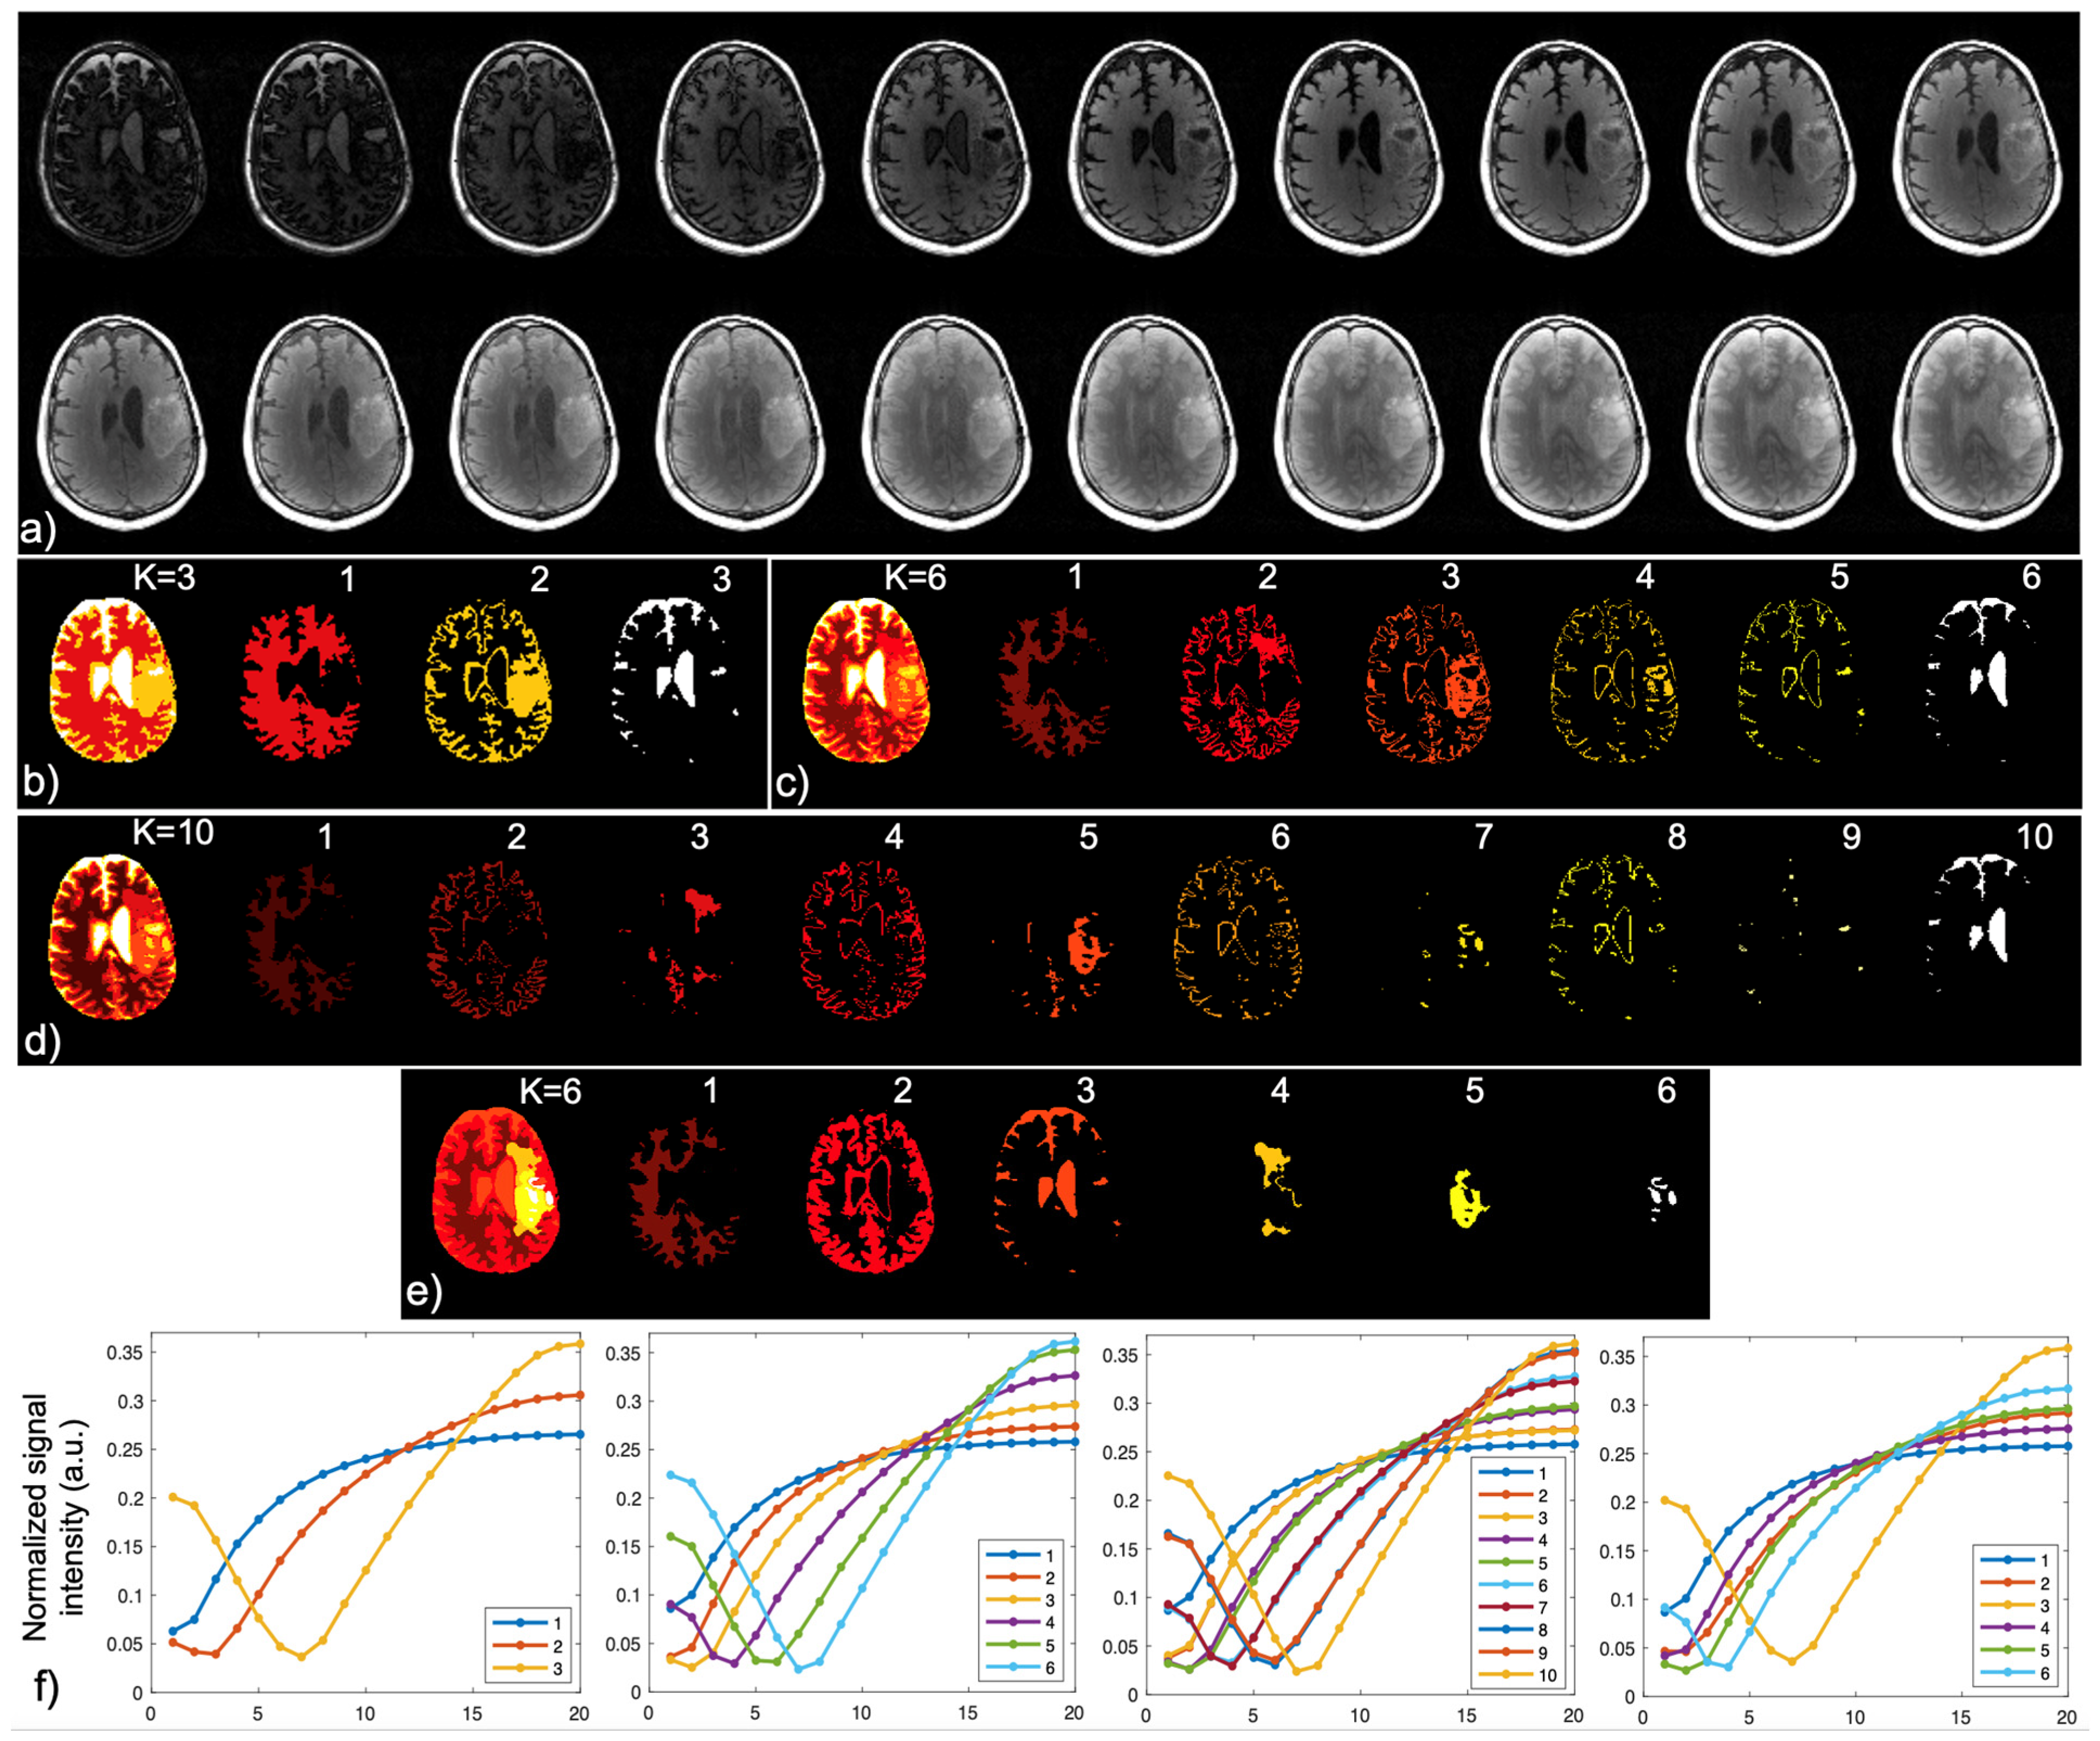

| Mapping | WM | GM | T2L-1 | T2L-2 | CEL | NEC |

|---|---|---|---|---|---|---|

| 2D T1 (ms) | 1186.4 ± 110.5 | 1589.5 ± 331.7 | 1451.5 ± 317 | 1657.9 ± 409.3 | 1947.8 ± 465.6 | 2022.3 ± 459.3 |

| 2D T2 (ms) | 90.4 ± 2.7 | 117.5 ± 12.8 | 114.7 ± 14.2 | 138.2 ± 21.3 | 153.4 ± 47.6 | 152.0 ± 41.1 |

| 3D MWF (%) | 30.4 ± 3.4 | 9.5 ± 3.3 | 12.5 ± 9.3 | 2.3 ± 1.8 | 0.55 ± 0.4 | 0.15 ± 0.0 |

| IIR-bSSFP T1 (ms) | 797.5 ± 88.3 | 670.4 ± 60.2 | 610.9 ± 58.1 | 598.4 ± 77.8 | 958.8 ± 204.9 | 1876.7 ± 608.8 |

| IIR-bSSFP T2 (ms) | 22.0 ± 5.7 | 85.2 ± 8.8 | 62.9 ± 26.5 | 115.4 ± 11.2 | 121.5 ± 10.1 | 157.5 ± 42.0 |

| IIR-bSSFP MF (%) | 14.9 ± 2.5 | 8.7 ± 1.9 | 11.9 ± 3.8 | 5.5 ± 2.6 | 3.6 ± 2.0 | 1.6 ± 0.5 |

| Mapping | CSF | WM | GM | T2L-1 | T2L-2 | CEL | NEC |

|---|---|---|---|---|---|---|---|

| IIR-bSSFP T1 (ms) | 2990.4 ± 277.4 | 848.0 ± 135.5 | 912.4 ± 218.4 | 749.5 ± 217.2 | 883.8 ± 238.8 | 1300.7 ± 303.4 | 2696.6 ± 749.7 |

| IIR-bSSFP T2 (ms) | 218.1 ± 14.9 | 28.5 ± 5.3 | 83.1 ± 20.9 | 62.2 ± 22.4 | 94.1 ± 29.1 | 115.8 ± 19.1 | 190.7 ± 31.9 |

| IIR-bSSFP MF (%) | 1.0 ± 0.4 | 10.0 ± 2.8 | 5.3 ± 1.3 | 7.8 ± 3.4 | 3.4 ± 1.3 | 2.6 ± 1.0 | 2.2 ± 1.2 |